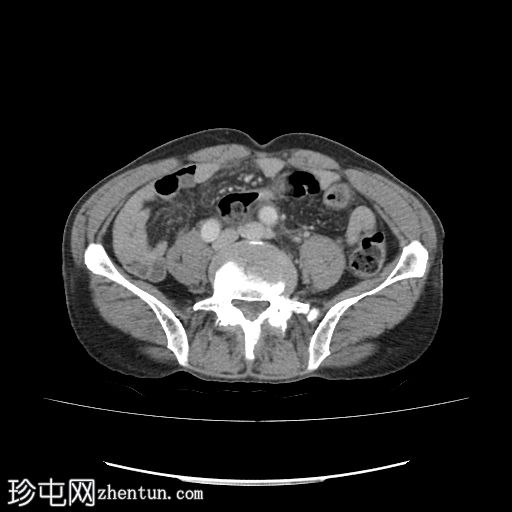

轴位增强扫描(门静脉期)

门静脉期(冠状位、矢状位)可见左侧肾周间隙少量积液,液体沿左侧髂腰肌向下走行。延迟期可见造影剂外渗至左侧肾周间隙,提示尿囊肿。

左侧近端输尿管结石导致中度肾积水,结石大小为0.8 x 0.6 cm,左肾可见一微小非梗阻性结石。

左肾多发性单纯性囊肿。最大的肿块尺寸为 4.4 x 3.8 厘米。

膀胱壁轻度增厚,提示膀胱炎。

前列腺轻度增大,体积约 40 毫升。

影像学上,尿瘤通常表现为肾周或腹膜后间隙的液体积聚。在本例中,延迟 CT 扫描清晰地显示造影剂从(肾盏/肾盂/输尿管)渗出并积聚在肾周间隙,证实了尿瘤的存在。